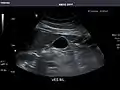

Right kidney

Kidneys: Right and left kidneys measure 11.5 cm and 12 cm in length respectively. No hydronephrosis. Small left lower pole kidney cyst.